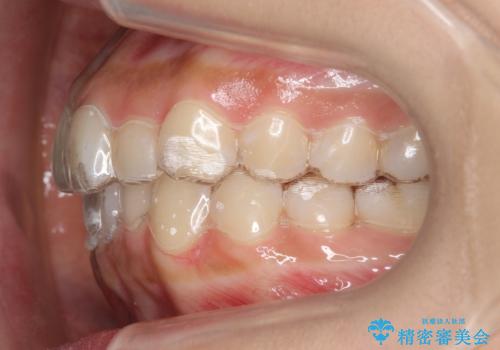

犬歯のねじれ 下の歯のがたがた インビザラインで

- 右上の犬歯のねじれ、下の歯のがたつきを主訴に来院。

インビザラインで歯を抜かずに並べました。

初回:上顎16ステージ 下顎22ステージ

リファインメント: 上顎23ステージ 下顎20ステージ

下の前歯のがたがたがそれなりにあったため、リファインメントを行いました。